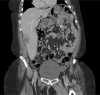

Introduction: Aseptic hepatic abscesses are a highly uncommon phenomenon and even more rare in the spectrum of extraintestinal manifestations of inflammatory bowel disease. Part of the spectrum of "neutrophilic disease," both the pathogenesis and the optimal management of these aseptic abscesses remain unclear. In the context of inflammatory bowel disease, sometimes these abscesses appear despite normal endoscopic findings.

Case presentation: We describe a highly uncommon case of aseptic hepatic abscess formation in a patient with inflammatory bowel disease.